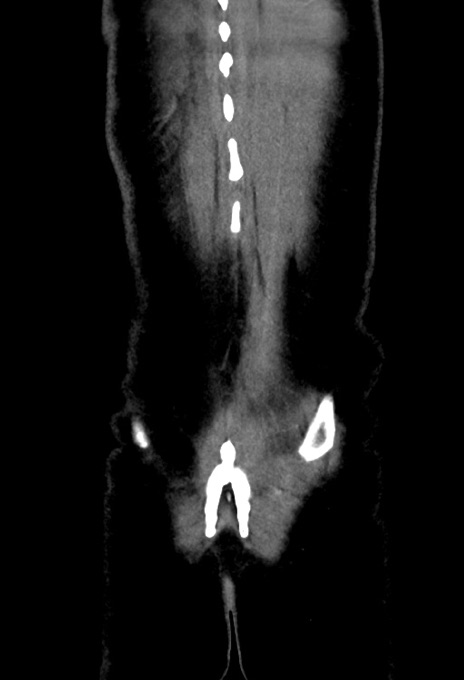

症例17(冠状断像)

【症例】20歳代女性

【主訴】嘔吐、下腹部痛

【現病歴】昨日夕食後に嘔吐し下腹部痛が出現。本日になっても嘔吐持続し改善しないため来院。

【身体所見】意識清明、BT 37.2℃、BP 108/67mmHg、腹部:平坦、やや硬、下腹部正中から右にかけて圧痛あり、反跳痛軽度あり、tapping pain(+)。

【データ】WBC 13600、CRP 14.94